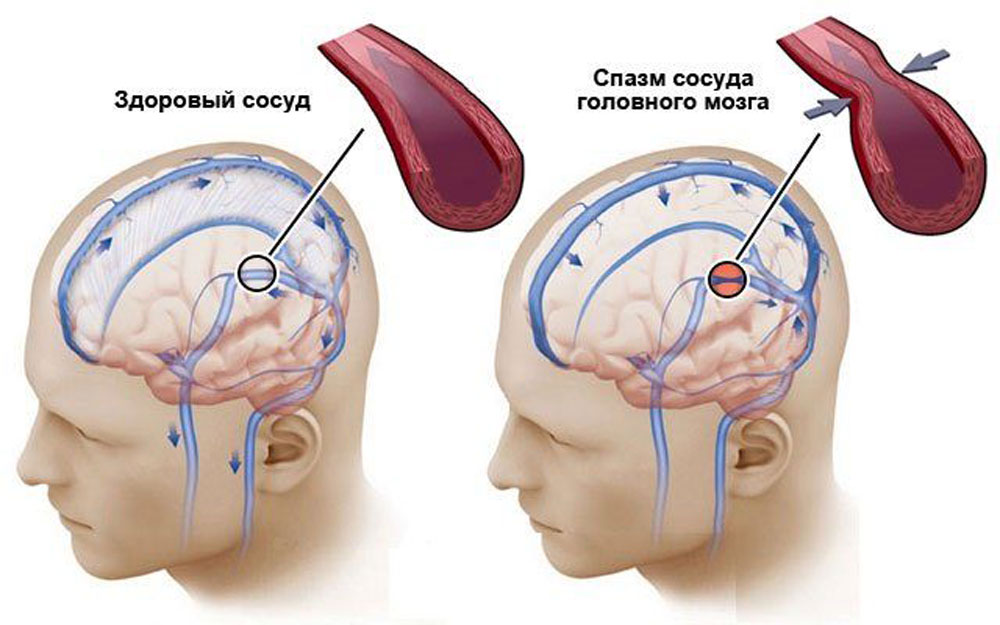

Хроническая ишемия головного мозга и лейкоареоз: симптомы и лечение